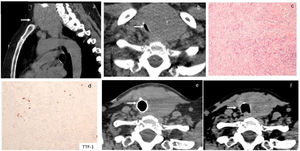

In the emergency department, acute global respiratory failure due to a diffuse goitre, which compromised the tracheal lumen, was identified. She required transient non-invasive ventilation, which restored oxygen saturation, and allowed further oxygen therapy via facial mask. Right tracheal deviation was firstly identified on chest X-ray. A voluminous goitre with intrathoracic extension (Fig. 1a) and a significant reduction in tracheal lumen with a minimal tracheal diameter of 3mm×10mm were identified on a chest computed tomography (CT) scan (Fig. 1b). Surgical treatment was proposed, and an exploratory cervicotomy was performed. During surgery, a fibrous thyroid gland highly adherent to adjacent structures was identified, which suggested a diagnosis of RT. Considering differential diagnosis with anaplastic thyroid carcinoma, intraoperative pathologic examination was performed, which also suggested RT. A decompressive isthmectomy was performed. The histopathologic report described thyroid tissue and surrounding soft tissues with infiltration by spindle cell proliferation, in a stroma with large collagen fibres, moderate lymphoplasmacytic inflammatory infiltrate and low eosinophil count; spindle cells had little nuclear pleomorphism and no mitoses were observed (Fig. 1c). In the immunohistochemistry study, focal positivity was observed for smooth muscle actin; there was negativity for cytokeratins AE1/AE3, TTF-1 (Fig. 1d), thyroglobulin, MDM2, ROS-1, pS100, desmin and CD34; (IgG)4+/IgG+ ratio did not suggest IgG4-associated disease. Analysis by FISH, with probes for detection of structural rearrangements of the ALK gene (Vysis ALK Break Apart FISH Probe Kit) did not reveal the rearrangement of the gene. A diagnosis of IgG4-related thyroid disease was excluded, given the histological and clinical absence of suggestive features. The definitive diagnosis was Riedel's thyroiditis and corticosteroid therapy with intravenous prednisolone (100mg/d) was started. Due to sustained compressive symptoms and oxygen need, a rigid bronchoscopy was performed five days after surgery and documented persistent extrinsic tracheal compression, with 70% lumen reduction. An endotracheal prosthesis restored tracheal lumen calibre and allowed resolution of symptoms. The patient was discharged two days after tracheal prosthesis placement, medicated with prednisolone per os 80mg/d, and did not require oxygen therapy.

At hospital admission, a chest CT scan revealed an exuberant diving goitre (a) with noticeable tracheal lumen reduction to 3mm×10mm (b). The histopathologic report described thyroid tissue and surrounding soft tissues with infiltration by spindle cell proliferation, in a stroma with large collagen fibres and moderate lymphoplasmacytic inflammatory infiltrate; spindle cells have little nuclear pleomorphism and no mitoses are observed (c, d). After 4 months of follow-up endotracheal prosthesis still provided airway safety (e). After 10 months of prednisolone treatment, thyroid size reduction allowed tracheal prosthesis to be safely removed (f).

At four months of follow-up in the endocrinology clinic, she remained asymptomatic, had good response to thyroid hormone replacement with levothyroxine, and no phosphocalcic metabolism disorders were present. Prednisolone was gradually reduced to 20mg/d. Tracheal prosthesis warranting airway safety and a reduction in thyroid size were documented by CT scan (Fig. 1e). After 10 months of diagnosis and glucocorticoid treatment, further thyroid size involution allowed tracheal prosthesis removal (Fig. 1f) without recurrence of symptoms.